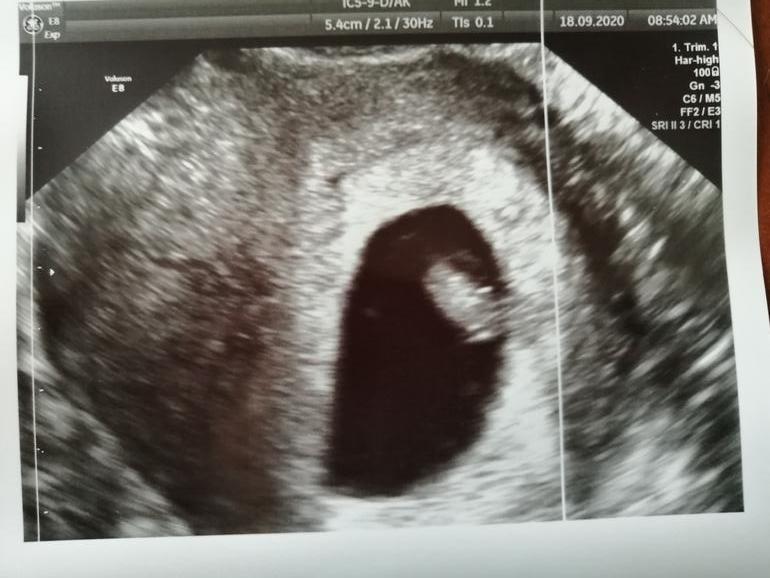

жду мальчика, 10 неделя

Первое узи 😍

Девочки, всем привет. Может кто то разбирается, по определению пола по прикреплению?)

Если УЗИ вагинальное было, то по теории Рамзи(если Вы о нем говорите, там пол определяется по прикреплению плаценты на определённой стороне ворсинок хориона) вероятнее всего, что девочка. Если УЗИ делали по животу, то мальчик.

Но там тоже есть процент вероятности))))) Так что не у всех достоверен результат!) У кого то совпадает, у кого то нет...

Ну если по Рамзи,то справа девочки)